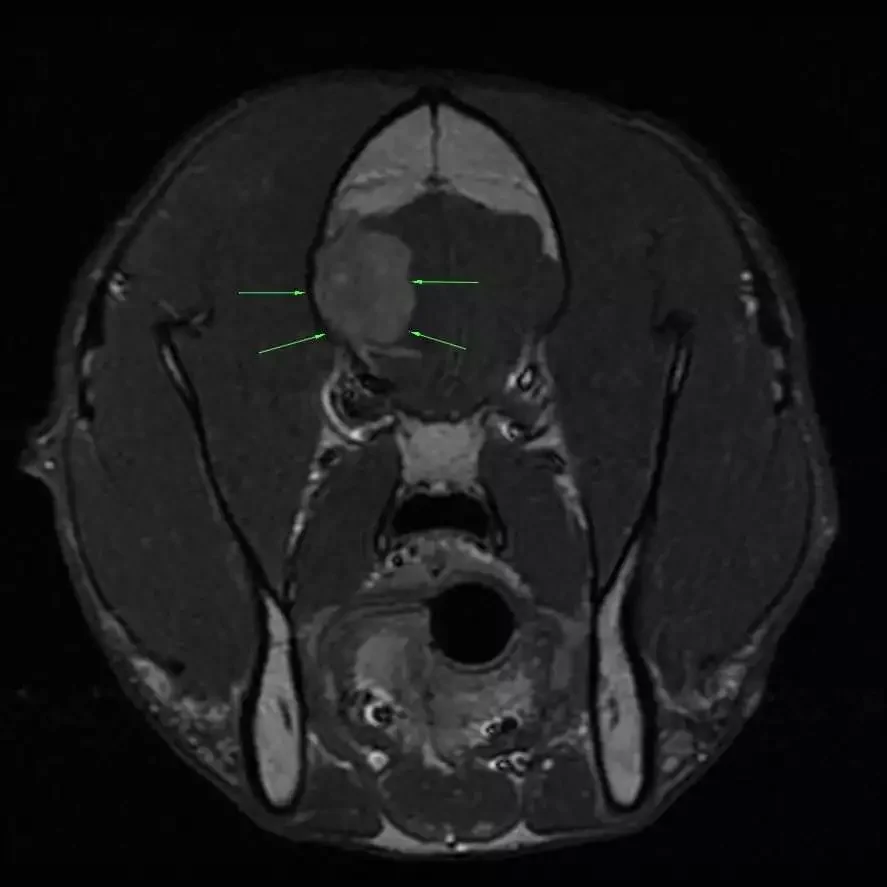

Pre-Operative MRI In Dog With Brain Tumor

The most common type of brain tumor in dogs and cats is called a meningioma. Meningiomas tend to be benign, located on the surface of the brain, and removable with surgery. This surgery can be curative for cats, while dogs can live for several years.

We will only recommend surgery if we feel that the potential for a good outcome outweighs the risks. After performing an MRI, your veterinary neurologist will let you know whether brain surgery is a good option for your pet.